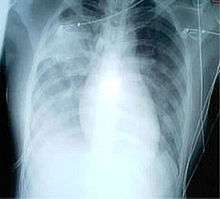

A chest X-ray showing increased opacity in both lungs, indicative of pneumonia, in a patient with SARS

For a case to be considered probable, a chest X-ray must be positive for atypical pneumonia or respiratory distress syndrome.

When it comes to the chest X-ray the appearance of SARS is not always uniform but generally appears as an abnormality with patchy infiltrates.[5]